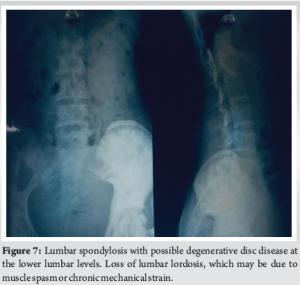

A 28-year-old woman arrived with a 20-year history of gradually increasing pain, swelling, and deformity of the left hemibody, particularly the lower limb, accompanied by functional scoliosis with right-side convexity. Symptoms first appeared in childhood. Upon examination, notable hypertrophy and joint stiffness were observed in the left lower limb (Fig. 1), with a 4.5 cm length discrepancy in the left lower limb, left-sided genu valgum, foot varus, and equinus deformity, along with hyperpigmentation and a scar over the left ankle. The skin over the lumbar region exhibited hyperpigmentation with a 4.5 cm soft tissue swelling at the L3 level (Fig. 2) and nodular thickening over the medial malleolus. Hip and knee fixed flexion deformities measured 25° and 90°, respectively. Digital radiographs and computed tomography (CT) scans demonstrated diffuse cortical thickening and hyperostosis affecting the pelvis, femur, tibia, talus, calcaneus, and tarsal bones of the left side, with partial joint fusion and medullary cavity obliteration, characteristic of “candle wax dripping” [4] (Fig. 3-7).